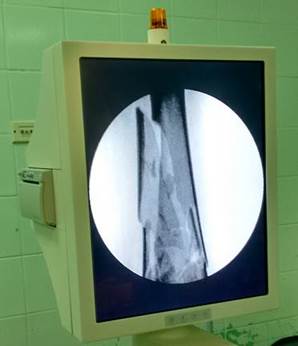

En el salón de operaciones una vez administrada anestesia general endotraqueal se colocó la paciente en la mesa ortopédica y se aplicó tracción. Se comprobó la alineación de la fractura mediante arco en “C” (Figura 2) y se procedió a colocar clavos de seis milímetros roscados en su punta, se colocaron tres proximales al foco de fractura en la región lateral del fémur, uno distal al foco de fractura del fémur y dos en la región anteromedial de la tibia, más tarde se colocaron barras dobles en los segmentos femoral y tibial, para después unirlas con dos barras (Figura 3).